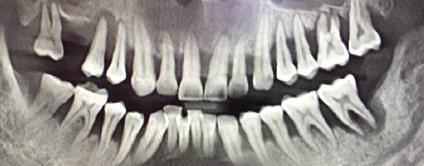

牙周炎是否嚴(yan) 重,需要檢查牙齒處於(yu) 哪個(ge) 階段?根據牙周炎的發展,一般可以分為(wei) 三種程度:

1、輕度牙周炎:這是前期,通常隻需要做規範的牙周治療,比如說一年或者半年定期到醫院洗牙,就能起到預防和治療牙周炎的作用。

2、中度牙周炎:多為(wei) 日常口腔衛生不好,從(cong) 來沒有洗牙的,這種情況除了需要做定期規範的洗牙,還需要做牙周深度刮治。

3、重度牙周炎:除了做牙周基礎治療,還需要進一步做手術翻瓣刮治,對於(yu) 嚴(yan) 重鬆動無法保留的牙齒可能需要拔牙處理(牙周炎造成的拔牙通常是多顆,甚至是半口、全口)。